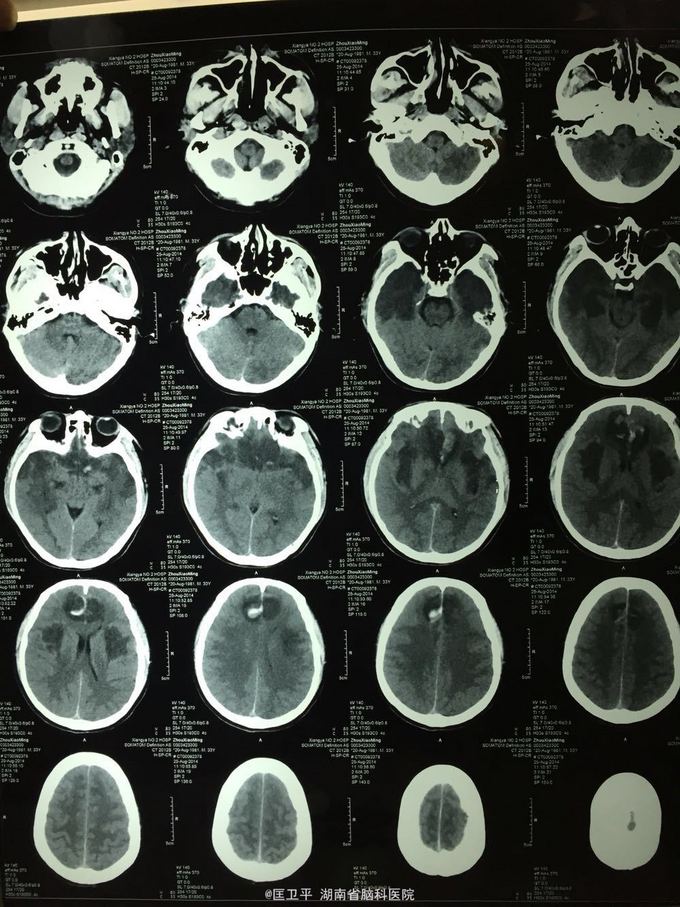

电击伤后智力低下,伤人毁物1年。 一年前在工地被电击伤昏迷,心跳呼吸停止,十几分钟后才有不规范的人工呼吸,持续约40分钟,心跳呼吸恢复。但患者智力低下,远近记忆很差,疑人害,伤人毁物严重,无法管理。

神清欠合作,五官无畸形,四肢活动正常,无神经定位体征。智能记忆很差,有被害妄想,有冲动攻击行为,无自知力,个人生活无法自理。